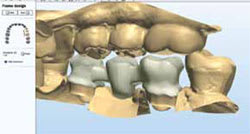

Full-contour wax crown designs were created starting with a default library tooth. Design adjustments were made with advanced shaping tools within the 3Shape software (Figure 9). 3Shape's Dental Designer software allows for multiple restorations, including multiple single units as well as bridges, on the same arch, to be designed simultaneously. This is a case that would have been extremely difficult to design using 3M ESPE's Lava Design software, which only allows for single unit or bridge designs.

Figure 11 Case 2 design. | Figure 12 Screen sharing and design collaboration session. | ||||||